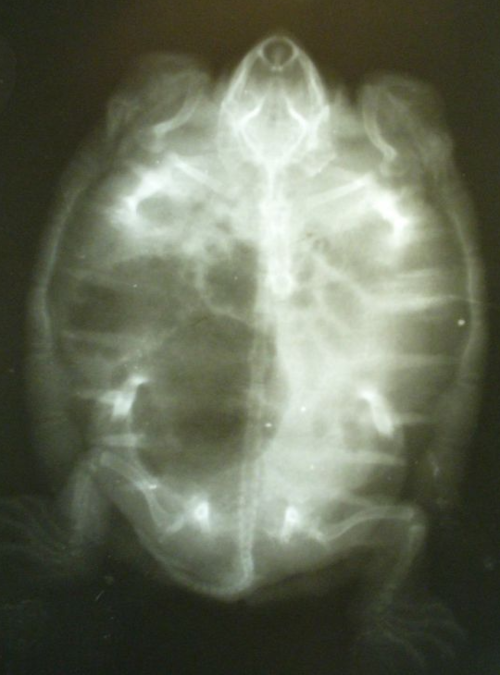

По поводу соплей - тут только делать рентген и смотреть лёгкие. Т.к. жидкость может быть и из желудка и из лёгких при пневмонии. К сожалению в Самаре у нас нет прям надёжного герпетолога, к кому можно обратиться без опасений, они иногда чудят и делают странные ненужные назначения или не те препараты https://cherepahi.ru/web/spravka/1196-spravochnik-samara

Вы можете сходить сделать рентген  в 3х проекциях (хотя бы в двух), чтобы оценить состояние легких, а сюда приложить снимки.

Спасибо огромное за ответ! В ближайшее время сделаю рентген и отправлю. Начинала лечить цитрациклиновой мазью на ночь и протирала хлоргексидином, отёчность глаз спала, но они так и не открылись